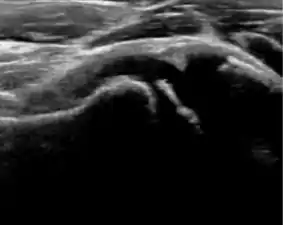

During childhood, ultrasound is a quick method to assess hip pain and quite often may be used to avoid use of irradiating techniques, such as radiography or CT. Ultrasound allows evaluation of joint effusion, synovial thickening and neovascularity, the bone/cartilage contour, and the femoral head-neck alignment. Although sonography is extremely sensitive in detecting increased synovial fluid, it is nonspecific and cannot be used with accuracy to determine the type of fluid. Transient synovitis of the hip, despite being the most frequent cause of pain in children between 3 and 10 years, remains a diagnosis of exclusion. It usually shows anechoic fluid, but echogenic fluid can also be found. The effusion is considered pathologic when it is measured at >2 mm in thickness. The differential diagnosis is wide, including osteomyelitis, septic arthritis, primary or metastatic lesions, LCPD, and SCFE. Discrimination from septic arthritis is challenging, often requiring joint aspiration. In septic arthritis, US is able to demonstrate a hip joint effusion, synovial thickening, and cartilage damage, although the appearances are nonspecific.[1]

A step between the head and the physis can be detected in children with SCFE, while abnormalities in the femoral head contour may suggest the presence of LCPD. In both cases, radiographs are mandatory to confirm diagnosis and severity (Figure 12).[1]

Figure 12:

Normal ultrasound appearance of the femoral head-neck junction.

Joint effusion in transient synovitis of the hip.

Flattening of the femoral head in a patient with Perthes disease.

Step in the femoral head-neck junction in a patient with SCFE.